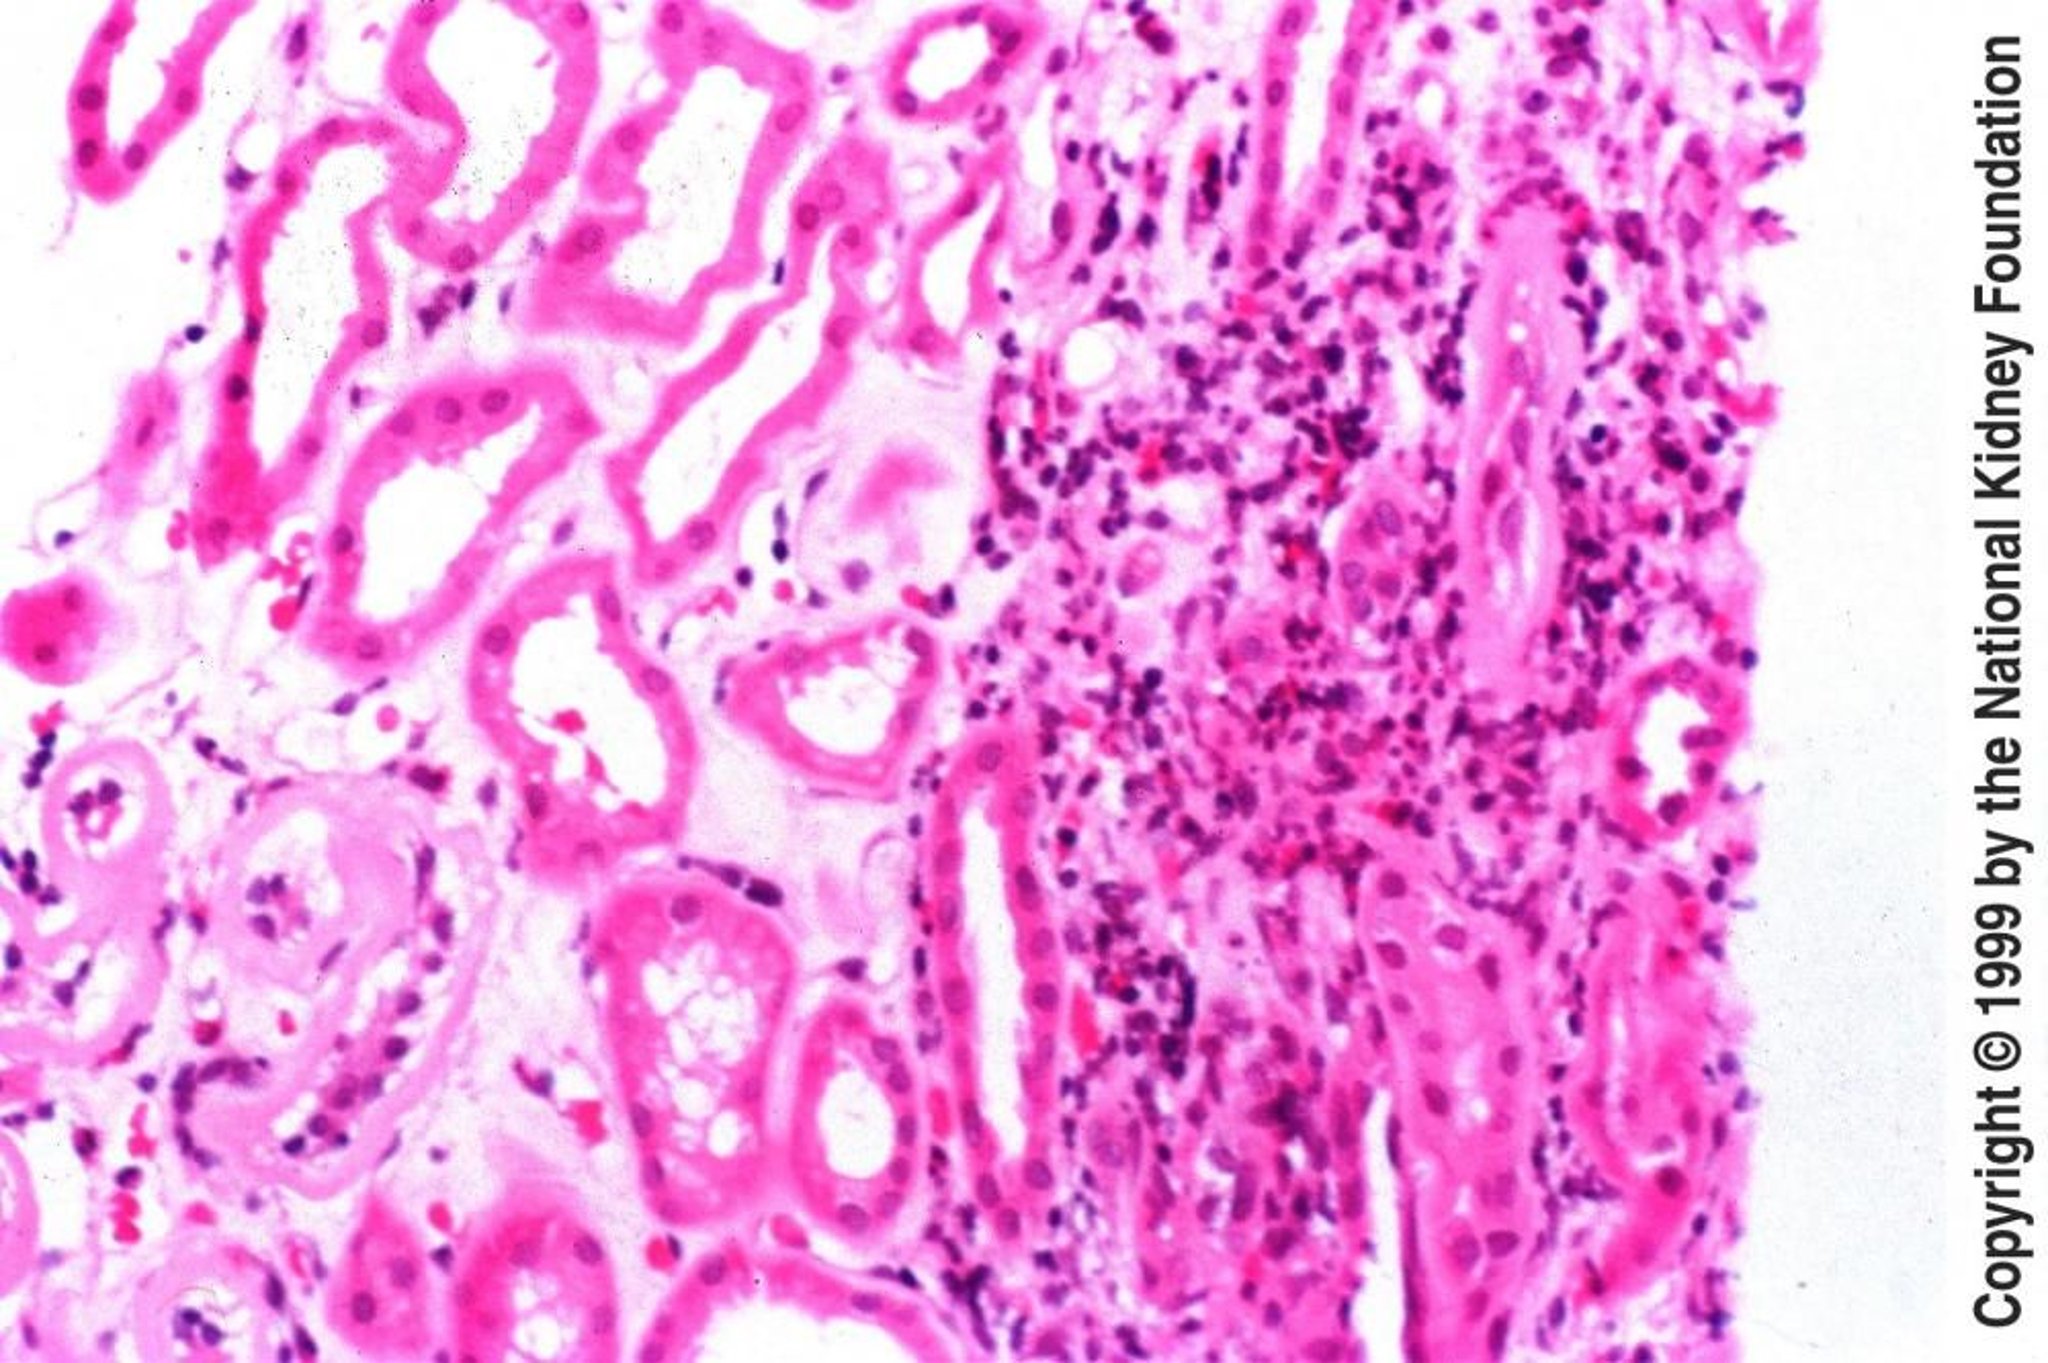

Nella nefrite tubulointerstiziale acuta, i glomeruli sono di solito normali. Il reperto più precoce è l'edema interstiziale, seguito tipicamente dall'infiltrazione interstiziale di linfociti, plasmacellule, eosinofili e alcuni leucociti polimorfonucleati. Nei casi gravi, si possono osservare le cellule infiammatorie invadere lo spazio tra le cellule che rivestono la membrana basale tubulare (tubulite); in altri campioni, si possono osservare reazioni granulomatose che derivano dall'esposizione ad antibiotici beta-lattamici, sulfamidici, micobatteri o miceti. La presenza di granulomi non caseosi è indicativa di sarcoidosi. Un'infiltrazione linfoplasmocitica dell'interstizio renale con fibrosi storiforme suggerisce una nefrite tubulo-interstiziale IgG4-correlata. L'immunofluorescenza o la microscopia elettronica raramente rivelano alterazioni patognomoniche.

Nella nefrite tubulointerstiziale cronica la biopsia renale non viene eseguita spesso a fini diagnostici. Tuttavia, se vi è preoccupazione per diagnosi alternative, potrebbe essere eseguita. I glomeruli variano da una situazione di normalità fino alla distruzione completa. I tubuli possono essere assenti o atrofizzati. I lumi tubulari variano in diametro, ma possono mostrare una marcata dilatazione con formazione di cilindri omogenei. L'interstizio contiene gradi variabili di cellule infiammatorie e fibrosi. Le aree non cicatrizzate appaiono quasi normali. Macroscopicamente, i reni sono piccoli e atrofici.